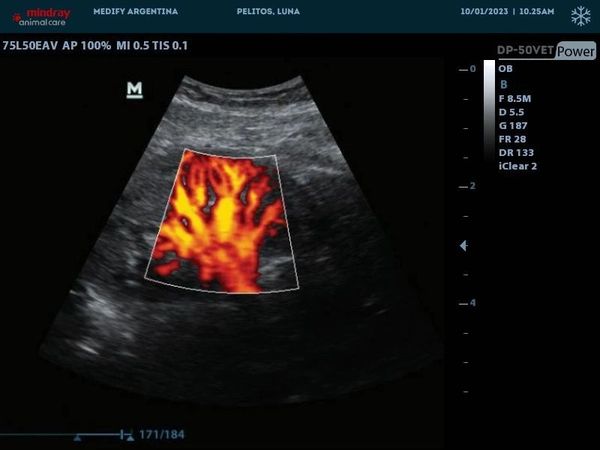

Proporciona información sobre la dirección y la velocidad del flujo sanguíneo en diferentes áreas del cuerpo del animal, lo que puede ayudar en el diagnóstico de condiciones vasculares y cardiacas.